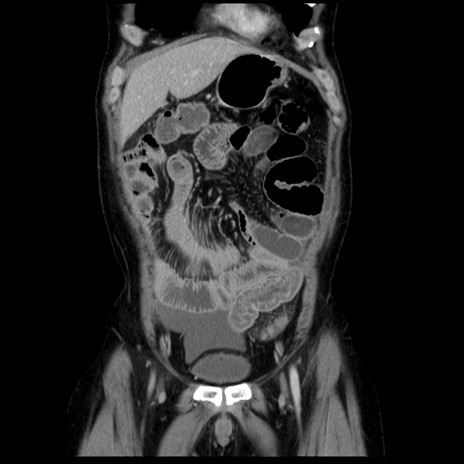

症例29(冠状断像)

【症例】40歳代男性

【現病歴】2日前から胃痛あり。徐々に周期的な激痛に変化した。本日になっても激痛があるため受診。

【身体所見】意識清明、BT 38-39℃台あり、腹部:膨満、やや硬、右下腹部に圧痛あり。

【データ】WBC 8500、CRP 23.26